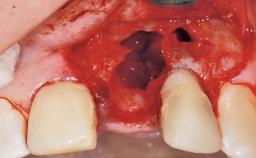

A 39-year-old male patient presented with a chief complaint of discomfort and gingival discoloration around his maxillary left central incisor. He was in good general health and was a non-smoker. His past dental history was significant because of the traumatic fracture of tooth 21 in a sporting accident at age 13. Initial dental treatment included endodontic therapy and a full-coverage restoration. The patient became symptomatic 5 years later, when structural failure of the tooth resulted in the dislodgment of the crown. Endodontic retreatment, apical surgery, and post-and-core restoration were performed.

Soft Tissue Anatomy Intact Defective

Bone Volume Horizontally and vertically sufficient Horizontally deficient Deficient vertically or deficient vertically AND horizontally

Soft Tissue Contour and Volume Slightly compromised